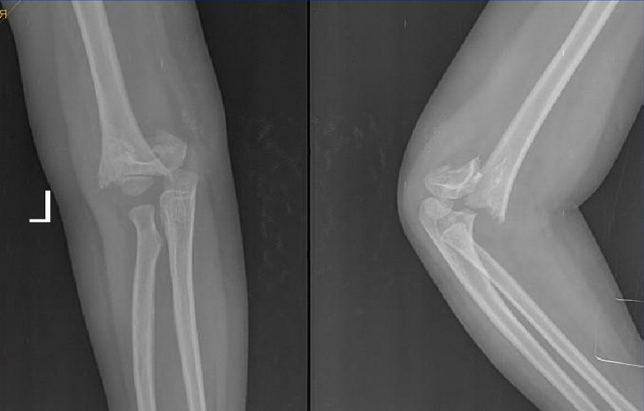

儿童肱骨髁上骨折位置

肱骨髁上骨折可分为伸直型、伸直尺偏型、伸直桡偏型和屈曲型。

1.伸直型

受伤时肘关节呈半屈位,手掌着地导致肱骨髁上部骨折,骨折的近侧端向前移位,远侧端向后移位。骨折线方向由后上向前下方斜形经过。移位严重者,骨折近侧端常损伤臂前方肌肉并对肱动脉造成损伤。

2.X线检查:可见骨折线。